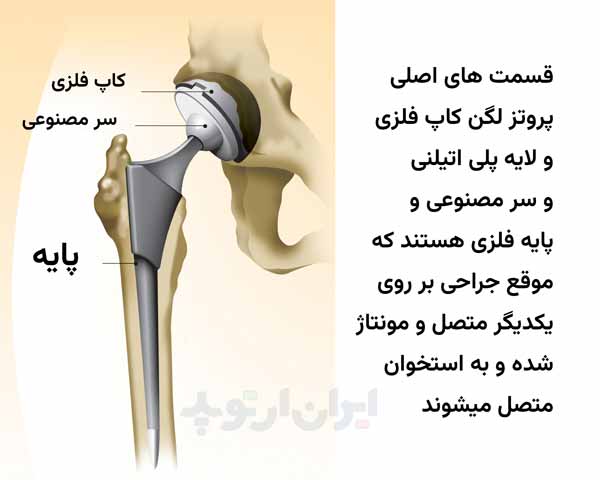

مفصل ران از کنار هم قرار گرفتن دو استخوان بوجود میاید. در قسمت بالا حفره استابولوم قرار دارد که قسمتی از لگن خاصره است. این حفره بشکل تقریبی یک نیمکره است. در داخل حفره استابولوم سر استخوان ران قرار گرفته است.

سر استخوان ران بالاترین قسمت استخوان ران است که به شکل گرد و کروی است. وقتی مفصل ران به علت آرتروز و یا روماتیسم خراب میشود معمولا هم قسمت کاسه ای یعنی حفره استابولوم و هم قسمت کروی یعنی سر استخوان ران هر دو خراب میشوند.

تعویض قسمت رانی: عمل جراحی تعویض مفصل لگن پزشک جراح سر استخوان ران را که خراب شده است از بدن بیمار خارج کرده و آنرا با یک کره یا گوی مصنوعی جایگزین میکند. این کره مصنوعی میتواند از جنس فلز یا سرامیک باشد.

اتصال این سر مصنوعی به باقیمانده استخوان ران با یک زائده به نام دسته Stem است که به سر مصنوعی متصل شده و پزشک جراح با قرار دادن دسته در داخل کانال مرکزی استخوان ران سر مصنوعی را در محل خود محکم میکند.

تعویض قسمت لگنی: جراح سپس سطح داخلی حفره استابولوم در ناحیه لگن را که خراب شده است با رنده های خاصی میتراشد. با این کار غضروف های خراب شده و استخوان های اضافه از داخل حفره استابولوم خارج شده و حفره به شکل یک نیمکره کامل درمیاید.

سپس یک کاسه فلزی به شکل نیمکره در داخل حفره آماده شده گذاشته شده و در داخل آن یک کاسه پلاستیکی از جنس پلی اتیلن قرار داده میشود.

مفاصل سیمانی و غیر سیمانی: در بعضی موارد ممکن است کاسه پلاستیکی بدون کاسه فلزی و تنها توسط یک چسب مخصوص به داخل حفره استابولوم چسبانده شود. به آن چسب، سیمان استخوانی Bone cement میگویند.

مفصل مصنوعی که برای اتصال آنها به استخوان از سیمان استخوانی استفاده میشود را مفصل سیمانی میگویند و اگر مفصل مصنوعی بدون کمک سیمان به استخوان متصل شود به آن مفصل سیمانی بدون سیمان یا سمنتلس cementless میگویند.

تکمیل جراحی تعویض مفصل لگن: پس از کارگذاری سر و کاسه مصنوعی، سر مصنوعی در داخل کاسه پلاستیکی قرار داده میشود تا بتواند در جهات مختلف در درون آن حرکت کند. این مجموعه سر و کاسه مصنوعی را پروتر لگن میگویند و به روش جاگذاری این مفصل مصنوعی در ناحیه لگن تعویض مفصل هیپ Hip Replacement یا توتال هیپ میگویند.